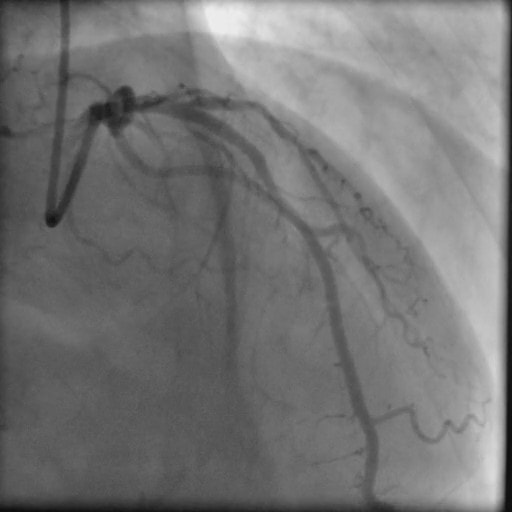

PCI後